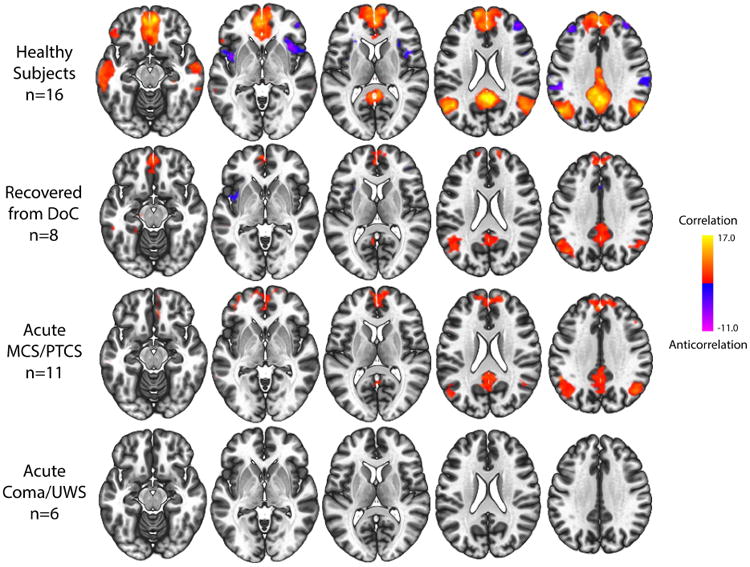

Personal Author:

Description:Integrity of the default mode network (DMN) is believed to be essential for human consciousness. However, the effects of acute severe traumatic brain injury (TBI) on DMN functional connectivity are poorly understood. Furthermore, the temporal dynamics of DMN reemergence during recovery of consciousness have not been studied longitudinally in patients with acute severe TBI. We performed resting-state functional magnetic resonance imaging (rs-fMRI) to measure DMN connectivity in 17 patients admitted to the intensive care unit (ICU) with acute severe TBI and in 16 healthy control subjects. Eight patients returned for follow-up rs-fMRI and behavioral assessment six months post-injury. At each time point, we analyzed DMN connectivity by measuring intra-network correlations (i.e. positive correlations between DMN nodes) and inter-network anticorrelations (i.e. negative correlations between the DMN and other resting-state networks). All patients were comatose upon arrival to the ICU and had a disorder of consciousness (DoC) at the time of acute rs-fMRI (9.2 ± 4.6 days post-injury): 2 coma, 4 unresponsive wakefulness syndrome, 7 minimally conscious state, and 4 post-traumatic confusional state. We found that, while DMN anticorrelations were absent in patients with acute DoC, patients who recovered from coma to a minimally conscious or confusional state while in the ICU showed partially preserved DMN correlations. Patients who remained in coma or unresponsive wakefulness syndrome in the ICU showed no DMN correlations. All eight patients assessed longitudinally recovered beyond the confusional state by 6 months post-injury and showed normal DMN correlations and anticorrelations, indistinguishable from those of healthy subjects. Collectively, these findings suggest that recovery of consciousness after acute severe TBI is associated with partial preservation of DMN correlations in the ICU, followed by long-term normalization of DMN correlations and anticorrelations. Both intra-network DMN correlations and inter-network DMN anticorrelations may be necessary for full recovery of consciousness after acute severe TBI.